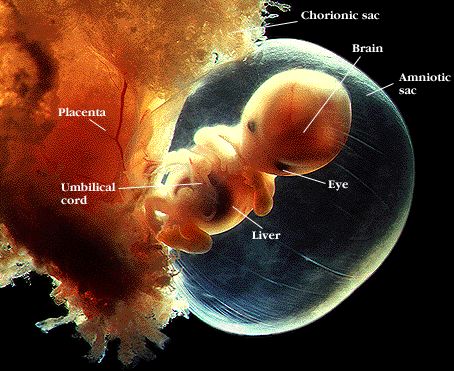

- Fóstrið er nú 16-18 mm og vegur örfá grömm.

- Höfuðuð er hlutfallslega stórt og er sveigt niður í átt að brjóstkassanum.

- Efri vör myndast ásamt nefbroddi.

- Augnalok verða sýnileg.

- Bygging hjartans er fullþróuð og hjartað slær u.þ.b. 150 slög á mínútu.

- Myndun innri kynfæra þ.e. eggjastokka og eistna hefst sem og myndun endaþarmsins.

- Í sónar má sjá fóstrið hreyfa sig en móðirin skynjar þessar hreyfingar ekki ennþá.